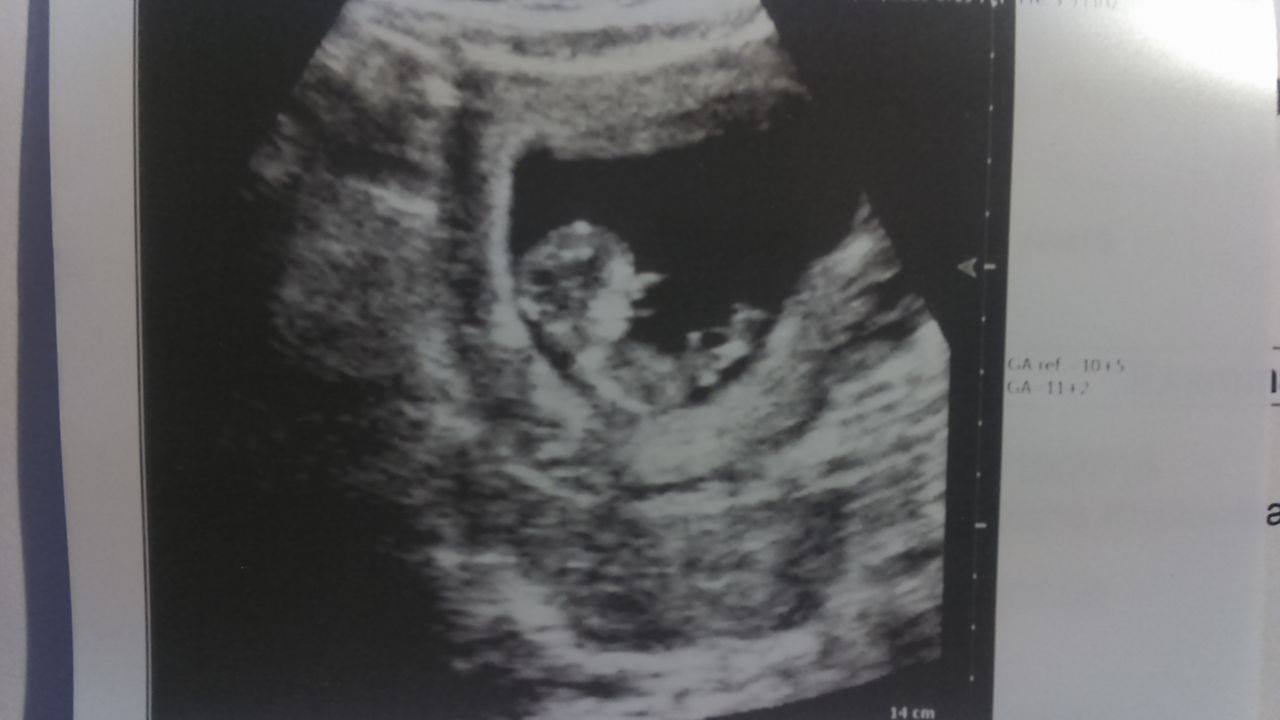

A to mój Pasażer na zdjęciu z wczoraj, 3.51 cm i nowa data porodu z usg - 7 maja. Serce bije, jest ok.

Mam umówione prenatalne na 26.10, ale dostałam też skierowanie na ust genetyczne w 20-22 tygodniu. Zawsze robi się dwa razy?